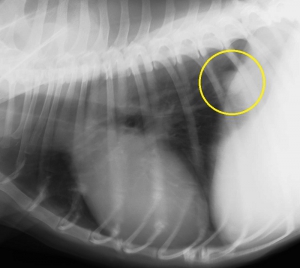

下2枚の写真は同じ犬の胸部レントゲン写真です。どちらも黄色の丸の中に白い円形の何かが見えると思います。

実はこの写真は肺転移した腫瘍のパターンなのですが、上のCRより下のDRの画像の方がよりはっきりと異常を確認できます。どちらも同じデジタルレントゲンなのですが、異常を際立たせるという意味でもDRに優位性があります。